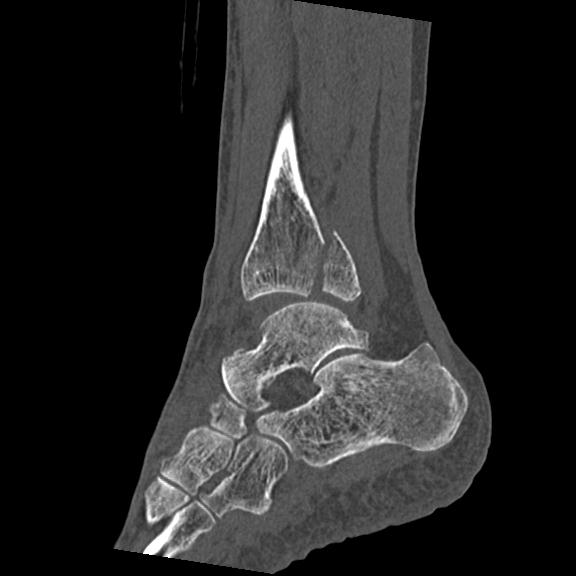

56476 8/28 4R 1/21 2R 左足関節 デジカメ写真 72歳女性 右足関節AS

102755 1/4 2R 1/15 2R 右足関節 68歳女性 右三果脱臼骨折